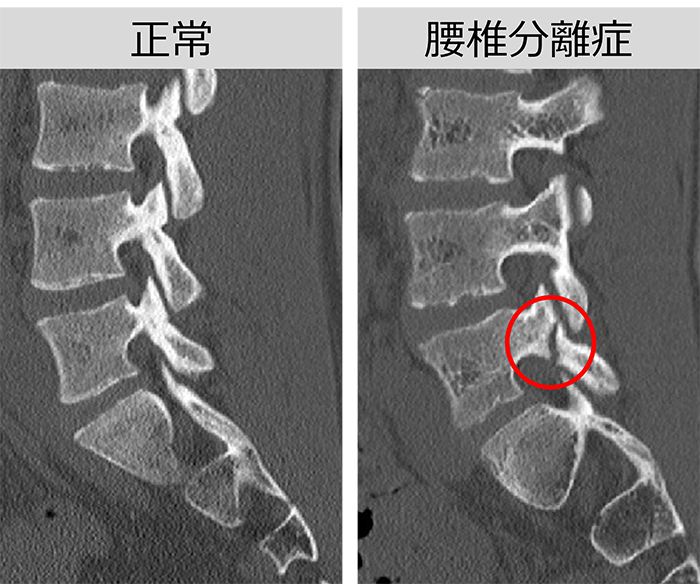

腰椎分離症は、スポーツや腰をひねる動作の繰り返しによって腰椎の後方に疲労骨折が起こるとされている状態です。

主に10代の成長期に多く、腰痛や下肢のしびれが出ると説明されており、一般の発症率は約5%、スポーツ選手では30〜40%といわれています。